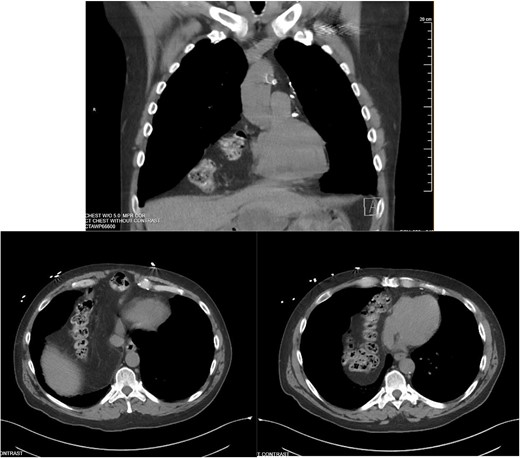

Approximately ten years prior, he had undergone coronary artery bypass surgery (CABG) with a xiphoidectomy. His symptoms at the time of the CT were right upper quadrant pain and epigastric fullness. He was referred for outpatient surgical evaluation. Shortly after the initial surgical assessment, he presented to the emergency department with gastric outlet obstruction. An abdominal CT was performed, showing a right-sided type 4 anterior diaphragmatic hernia with herniation of the antrum and pylorus causing the obstruction (Fig. 2). A loop of the transverse colon was also herniated into the thorax but without colonic obstruction.

Right-sided type 4 anterior diaphragmatic hernia with antrum and pylorus herniation.